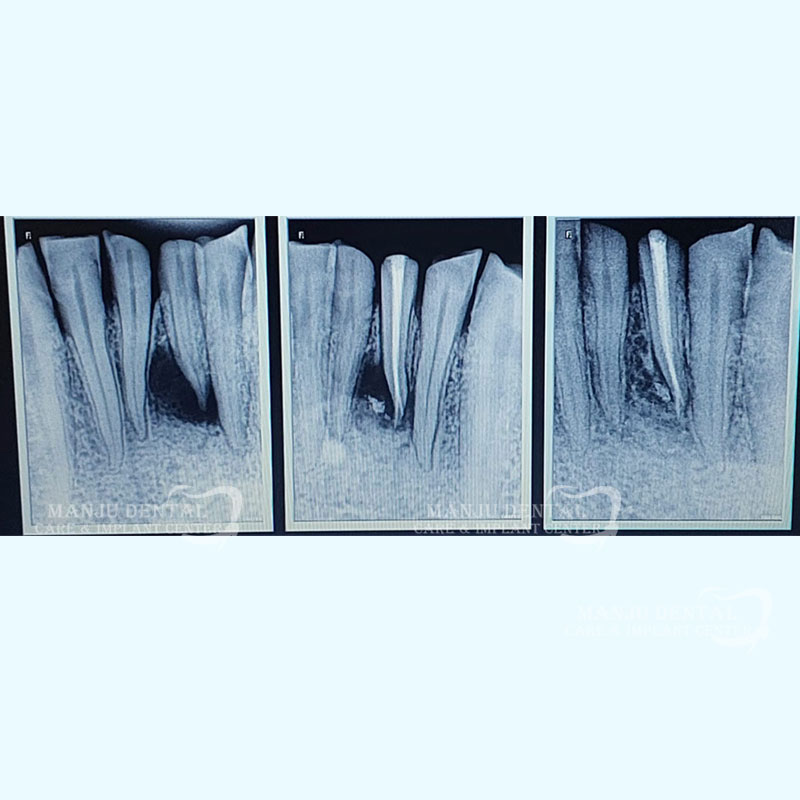

Hopeless Teeth Restored With Endodontic Treatment

1.  After clinically examining the tooth, a radiograph is done using x-rays and  local anaesthesia is administered to make tooth numb. An assess opening is done to enter pulp chamber and very small instruments are used to clean the pulp from the chamber and root canals of the tooth.

2. After the space is cleaned and shaped, the root canals are filled with a biocompatible material called gutta-percha. The gutta-percha is placed with a endodontic sealer to ensure complete 3D obturation of the root canal system. After obturation a permanent restoration is done to completely seal the tooth.

If the tooth lacks sufficient structure to hold the restoration in place, a post may be needed inside the tooth and post and core procedure is done to give strength to the remaining tooth structure.